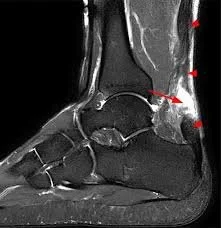

Diagnosis of Achilles Tendon Rupture

Diagnosis is based on a detailed history and physical examination. Common findings include weakness with plantarflexion and, in some cases, a palpable gap in the tendon. Ultrasound or MRI may be obtained to confirm the diagnosis, assess the extent of the tear, and guide treatment decisions.